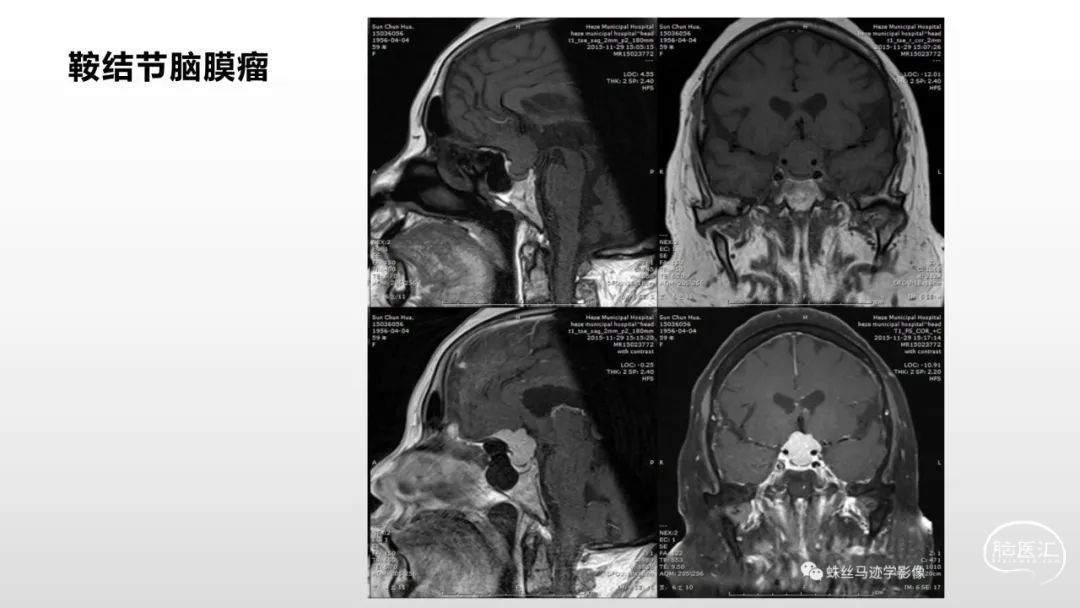

颅脑影像诊断基础知识讲座:脑膜病变